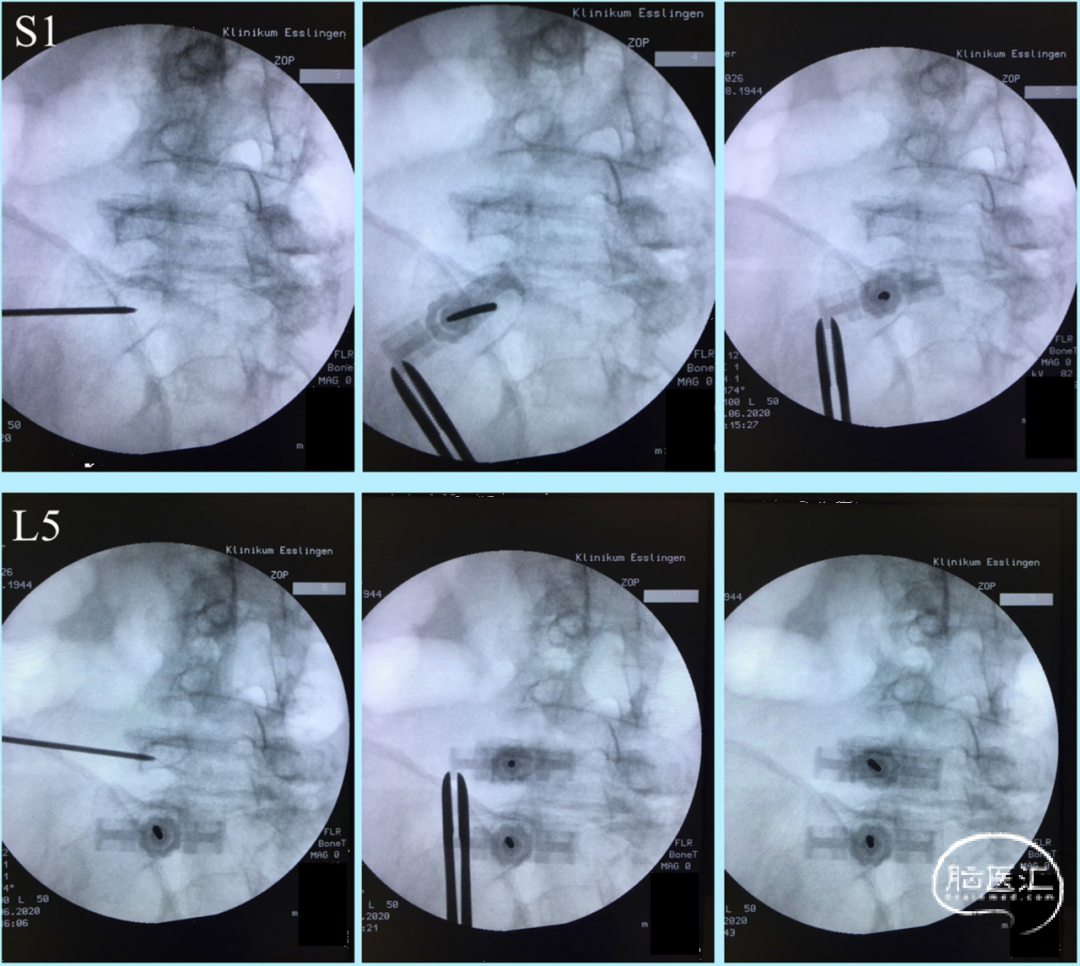

侧卧位透视下椎弓根螺钉放置可通过不同的C形臂位置或旋转手术床位置进行控制(图1、2)。

侧卧位旋转手术台10-30°(而不是C臂转动)也可在隧道视图指示下放置椎弓根螺钉(图3、4、5、6)。

图3. 经皮椎弓根螺钉放置术,手术台向后旋转用于置入上排椎弓根(左),向前旋转用于置入下排椎弓根(右)。